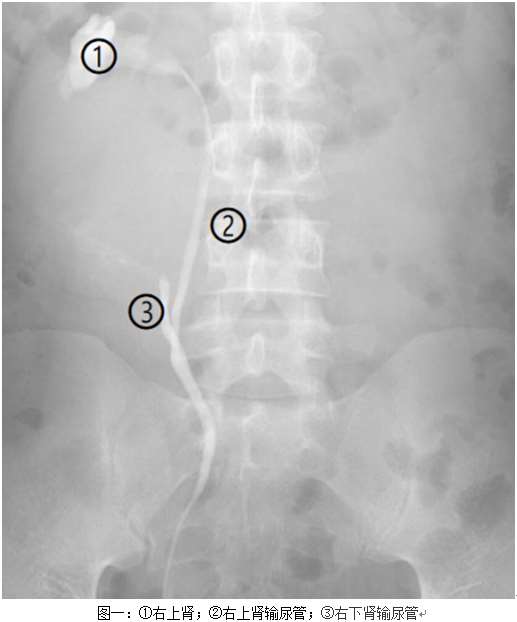

近日,泌尿外科收治一男性患者,该病人于外院诊断为肾囊肿,拟入我科行手术治疗,要求刘川教授亲自主刀。患者入院后,我院CT检查提示马蹄肾、双肾囊肿(右肾较大),左侧输尿管结石。基于多年的临床经验,刘川教授、胡自力教授在阅片时敏锐地发现患者极有可能不是单纯的马蹄肾合并右肾囊肿,更像是肾积水。刘川教授和胡自力教授决定暂缓患者手术,先完善逆行尿路造影造影。逆行尿路造影提示(图一):右侧双肾盂、输尿管显示,考虑重复肾,并右下肾盂重度扩张、积水。马蹄肾和重复肾我科都有多年的治疗经验,但马蹄肾合并重复肾并不多见,刘川教授让全组人员集体查找文献,探讨最佳治疗方案。